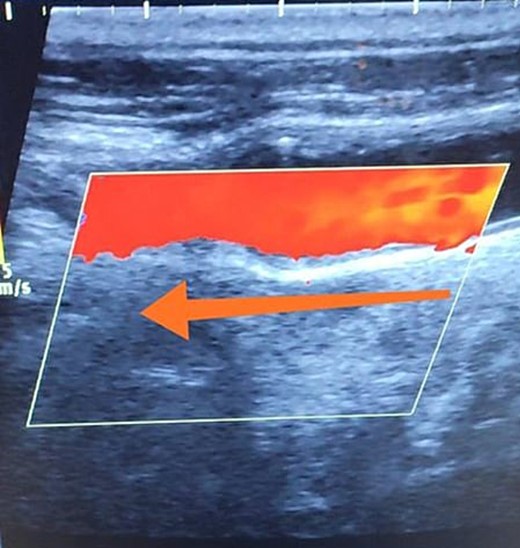

A 65-year-old male presented with recurrent transient ischemic attacks (TIAs), characterized by severe balance disturbances, transient alterations in consciousness, and visual obscurations. Clinical examination revealed high blood pressure in the right arm and absent left radial and brachial artery pulses. Vital signs were normal. Laboratory tests are analyzed as follows: urea: 22 mg/dl, glucose: 150 mg/dl, cholesterol: 199 mg/dl, and triglycerides: 222 mg/dl. A medical history of type 2 diabetes mellitus (DT2), hypertension (HTN), hyperlipidemia, ischemic heart disease, and a heavy smoking history were recorded. Five years before presentation, the patient underwent coronary stenting. Medication history included metformin 1000 mg, aspirin 81 mg, rosuvastatin 40 mg, and ramipril 5 mg. Neck duplex ultrasound (DU) showed normal flow direction and insignificant atherosclerotic plaques in the left internal carotid artery (CA) and left external CA (Figs 1 and 2), normal common CA (Fig. 3), a completely inverted flow direction in the left VA (Fig. 4) that suspected a significant ostial lesion in the left SCA. Multi-slice computed tomography angiography demonstrated 99% stenosis at the left SCA origin and confirmed the presence of SSS (Fig. 5). A balloon angioplasty was unsuccessfully attempted to expand the left SCA. A left carotid VA bypass surgery was performed, and a vascular graft was used to establish a blood flow pathway between the left VA and the left CA. By follow-up, the patient was stable without complications.

Duplex ultrasound showing a normal flow direction and insignifcant atherosclerotic plaques in the left internal carotid artery.

Duplex ultrasound showing a completely inverted flow direction in the left vertebral artery.

With a prevalence ranging from 0.6% to 6.4%, SSS is considered a rare phenomenon, and high suspicion is required for diagnosis [2, 5]. The basilar artery is formed by the two vertebral arteries and connects to the brain’s anterior circulation, comprising the Willis circle. However, a steno-occlusive lesion of the proximal SCA may lead to limited blood flow to the upper extremity. Consequently, blood flows through the contralateral VA to the basilar artery, around the circle of Willis, and then descends through the IVA to supply the affected upper extremity, leading to upper limb and vertebrobasilar insufficiency. This altered physiology manifests in signs and symptoms constellation defining SSS [1, 4]. A total of 82.3% of lesions primarily affect the left side as a result of the sharper curvature at the origin of the left SCA, which increases blood flow turbulence and promotes atherosclerotic plaque formation [1, 2, 5–7]. In this case, a patient with retrograde left VA flow on DU is presented (Fig. 4). Most patients are asymptomatic due to developing collateral circulation [2]. However, it may manifest with arterial insufficiency affecting the upper limb (paresthesia, weakness, and claudication), the brain (vertigo, dizziness, diplopia, ataxia, dysarthria, slurred speech, and syncopal episodes) [1, 2, 5, 7], or the heart if the patient has a coronary artery bypass graft supplied by the internal mammary artery [6]. Our patient suffered from recurrent TIA, manifested as severe balance disturbances, transient altered mental status, and amaurosis fugax (transient vision loss). The most common diagnostic tests for SSS are the DU and TDU due to their accessibility and low cost, which show the subsequent retrograde blood flow in the IVA. Additionally, MRA or CT angiography is used as a confirmatory modality [1, 2, 5–8], but the gold-standard is conventional cerebral angiography [1]. A difference in blood pressure readings between arms >20 mmHg is a significant and noticeable sign. In our case, neck DU showed an inverted left VA flow direction (opposite to the carotid) (Fig. 1). MSCT confirmed the diagnosis of SSS, demonstrating a significant ostial lesion in the left SCA. Conservative management is preferred with minimally symptomatic patients by reducing risk factors like a specific regime and treating comorbidities such as: HTN, DT2, hyperlipidemia, and smoking cessation as a part of minimizing morbidity and preventing complications [1, 2, 5–8]. Surgery is recommended for severe and untreated cases through percutaneous intervention or surgical revascularization by using vascular bypass accompanied by angioplasty and stenting [1, 2, 5–7]. In our case, expanding the left subclavian by catheterization did not succeed; however, a left carotid-vertebral bypass was successfully performed. The most common complications are stroke (ranging from 0.4% to 4.7%) due to distal emboli, thrombosis or bleeding and rupture because of aggressive catheter or wire manipulation [1, 7]. In our case, the patient continues on HTN and DT2 medications: ramipril 5 mg, rosuvastatin 40 mg, aspirin 81 mg, and metformin 1000 mg.